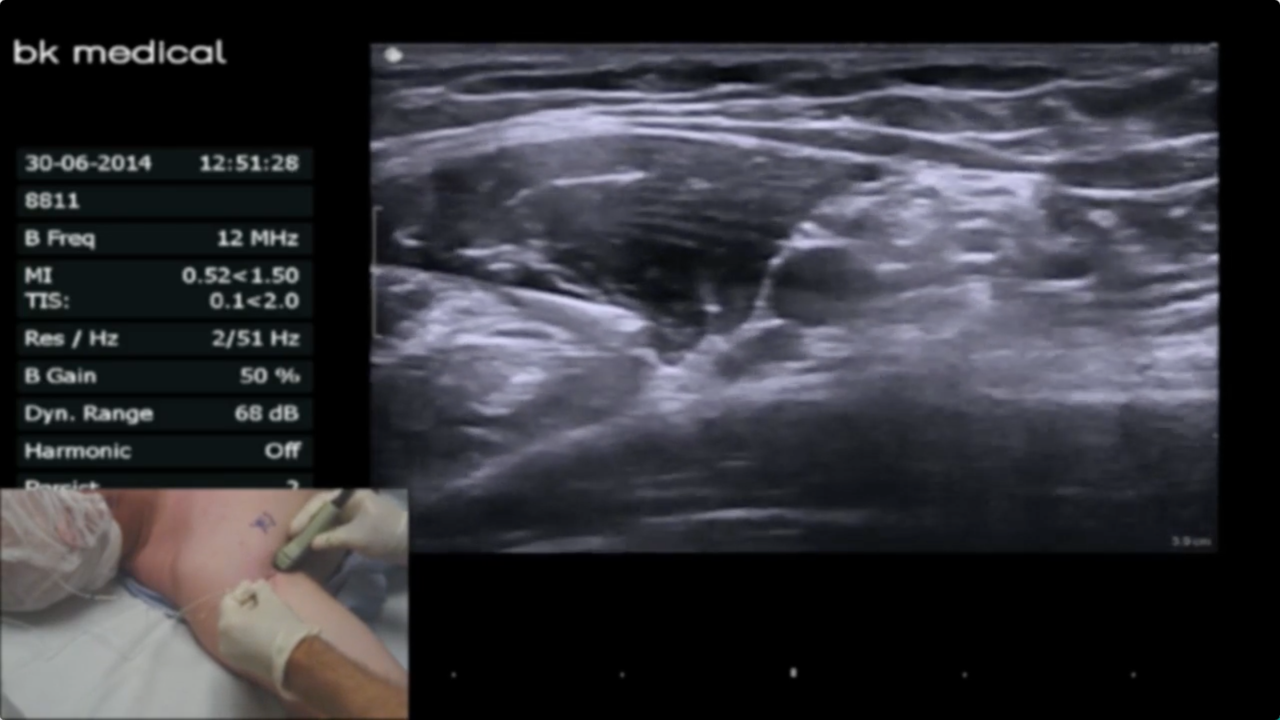

Late Branching Musculocutaneous NerveIn this video by Dr. Saad Kamal, with an introduction by Dr. Brandon Winchester, we demonstrate an important anatomic variation occasionally found during axillary brachial plexus blocks: a late branching musculocutaneous nerve off the lateral cord. When this variation occurs it results in difficu...

Axillary Virtual Ultrasound WorkshopIn this new Virtual Ultrasound Workshop video Dr. Brandon Winchester explains tips and tricks for the successful and safe placement of axillary brachial plexus blocks. The BLOCKJOCKS Virtual Ultrasound Workshop comprehensively discusses and demonstrates scanning & technique considerations for ...

Ultrasound-Guided Axillary Brachial Plexus BlockBrandon Winchester performs an ultrasound-guided axillary brachial plexus block with an axillary ring infiltration for a distal biceps tendon and carpal tunnel release.

Axillary BlockBlock of the Day #10: Brandon Winchester performs an US-guided axillary block for finger/wrist surgery at Andrews Institute.